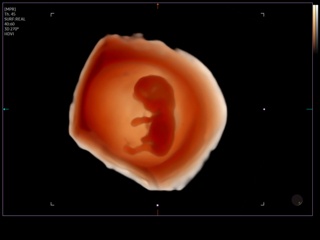

Atlas of ultrasound images - obsterics

In the section "Оbsterics" of atlas the results of ultrasonic examinations of pregnant women with different durations of gestation are represented. Here you can see images of internally organs, cerebrum, cordis and the sex of the fetus, the sonograms of multiple pregnancy, the blood flow in placenta and umbilical cord, defects of fetal`s development, etc.